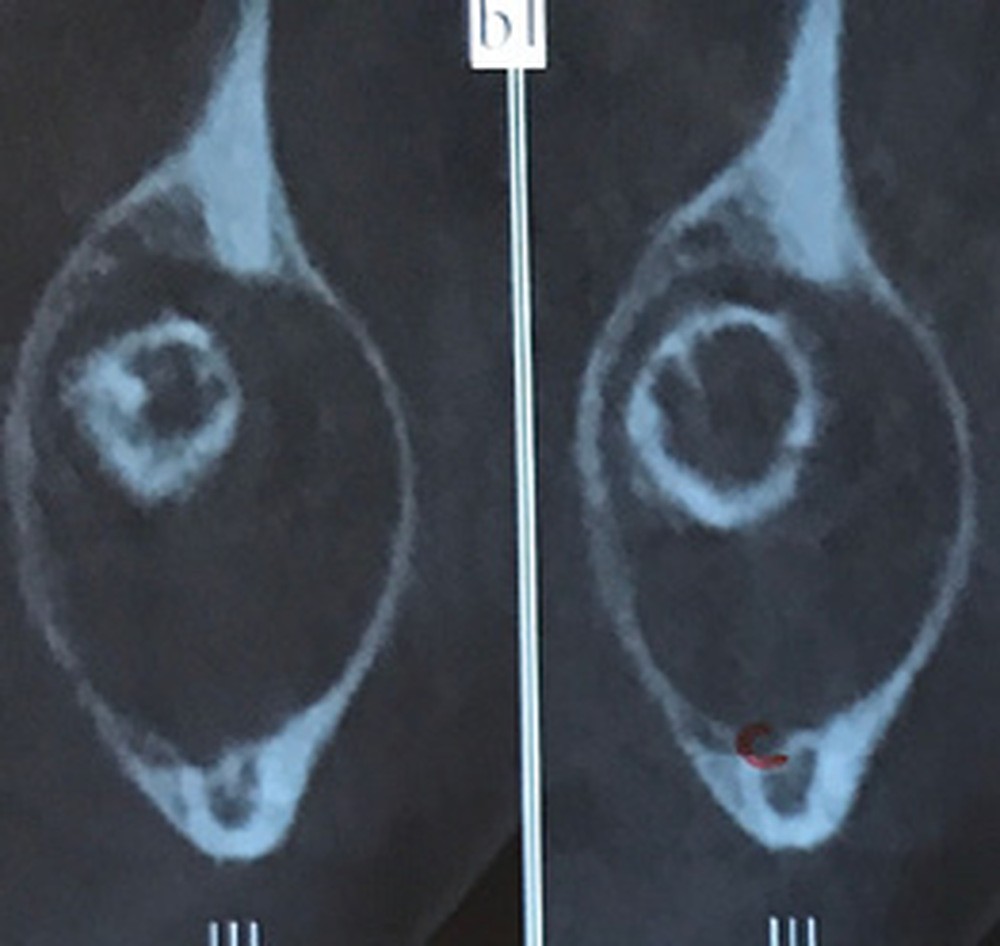

Les kystes et tumeurs bénignes osseuses maxillaires ou mandibulaires chez l’enfant sont le plus souvent asymptomatiques. Ces lésions osseuses sont découvertes de façon fortuite lors d’un bilan radiographique de routine réalisé par l’odontologiste pédiatrique ou l’orthodontiste [1-3]. Néanmoins, des lésions peuvent parfois se développer rapidement et être destructrices [1, 2]. Certains signes cliniques spécifiques à la chronologie de l’éruption dentaire chez l’enfant doivent nous alerter tels qu’un retard d’éruption dentaire ou une éruption dentaire asymétrique (fig. 1). D’autres manifestations cliniques, moins spécifiques à l’enfant, peuvent également orienter le clinicien sur la présence d’une pathologie osseuse sous-jacente : mobilité dentaire, douleur, tuméfaction, limitation de l’ouverture buccale, trouble neurosensoriel, etc. [3]. C’est la radiographie panoramique qui va ensuite mettre en évidence/confirmer la présence d’une lésion intra-osseuse (fig. 2).

La radiographie panoramique permet une première interprétation de la lésion osseuse (localisation, nombre, taille approximative, etc.). Cet examen est souvent complété par un bilan d’imagerie en trois dimensions de type Cone Beam [4]. Il précisera le volume et les limites de la lésion ainsi que ses rapports avec les structures anatomiques avoisinantes (tableau 1). Ces données radiologiques confrontées à l’examen clinique et à la fréquence relative des lésions permettent de réaliser un diagnostic d’intuition qui orientera la prise en charge.